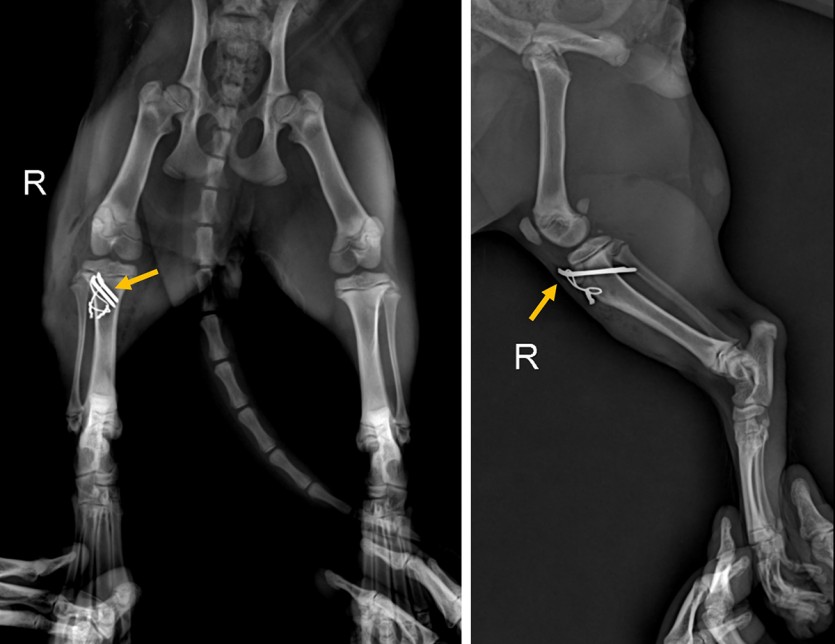

<수술 후 방사선 사진 : 핀과 와이어를 이용해 골절편 고정. 골절면이 잘 맞아 제 위치에 고정된 것이 확인된다>

<수술 후 2주차 사진 : 방사선_핀과 와이어가 잘 유지되고, 골절선이 점차 사라지고 있는 것이 확인된다>

수술 후 방사선 상 골편이 잘 고정된 것이 확인되었고, 귀여운 냥이는 일주일간 재활치료를 동반한 입원치료를 씩씩하게 잘 받았습니다.

붕대를 하지 않은 상태에서도 다리를 잘 딛으며 걷는 것이 확인되어 퇴원했습니다.